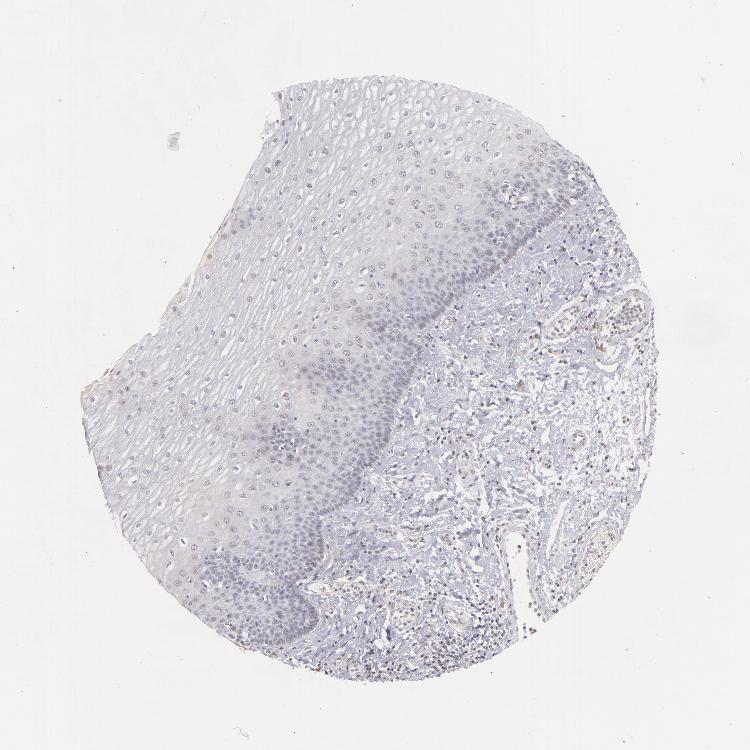

ESOPHAGUS - Antibody stainingi

Antibody staining in the annotated cell types in the current human tissue is reported as not detected, low, medium, or high, based on conventional immunohistochemistry profiling in selected tissues. This score is based on the combination of the staining intensity and fraction of stained cells.

Each image is clickable and will lead to virtual microscopy that enables deeper exploration of all samples and also displays staining intensity scores, fraction scores and subcellular localization as well as patient and tissue information for each sample.

Antibody HPA001586

Squamous epithelial cells Not detected